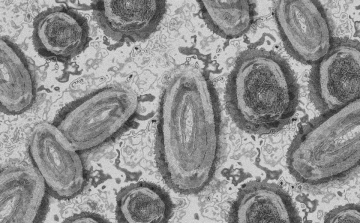

Hantavírus - Megkezdődött a Hondius utasainak evakuálása Tenerifén

Megkezdődött a Hondius holland óceánjáró utasainak evakuálási folyamata Tenerife szigetén - jelentette be a spanyol egészségügyi miniszter a kikötőben tartott sajtótájékoztatón vasárnap reggel.